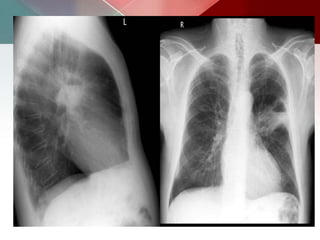

c) Cavitating Pulmonary tuberculosis:

 Post-primary infections are far more likely to cavitate

than primary infections and are seen in 20-45% of

cases.

 In the vast majority of cases, they develop in the

posterior segments of the upper lobes (85%).

 The development of an air-fluid level implies

communication with the airway, and thus the

possibility of contagion.

 Endo-bronchial spread along nearby airways is a

relatively common finding, resulting in a relatively

well-defined 2-4 mm nodules or branching lesions

(tree-in-bud sign) on CT.